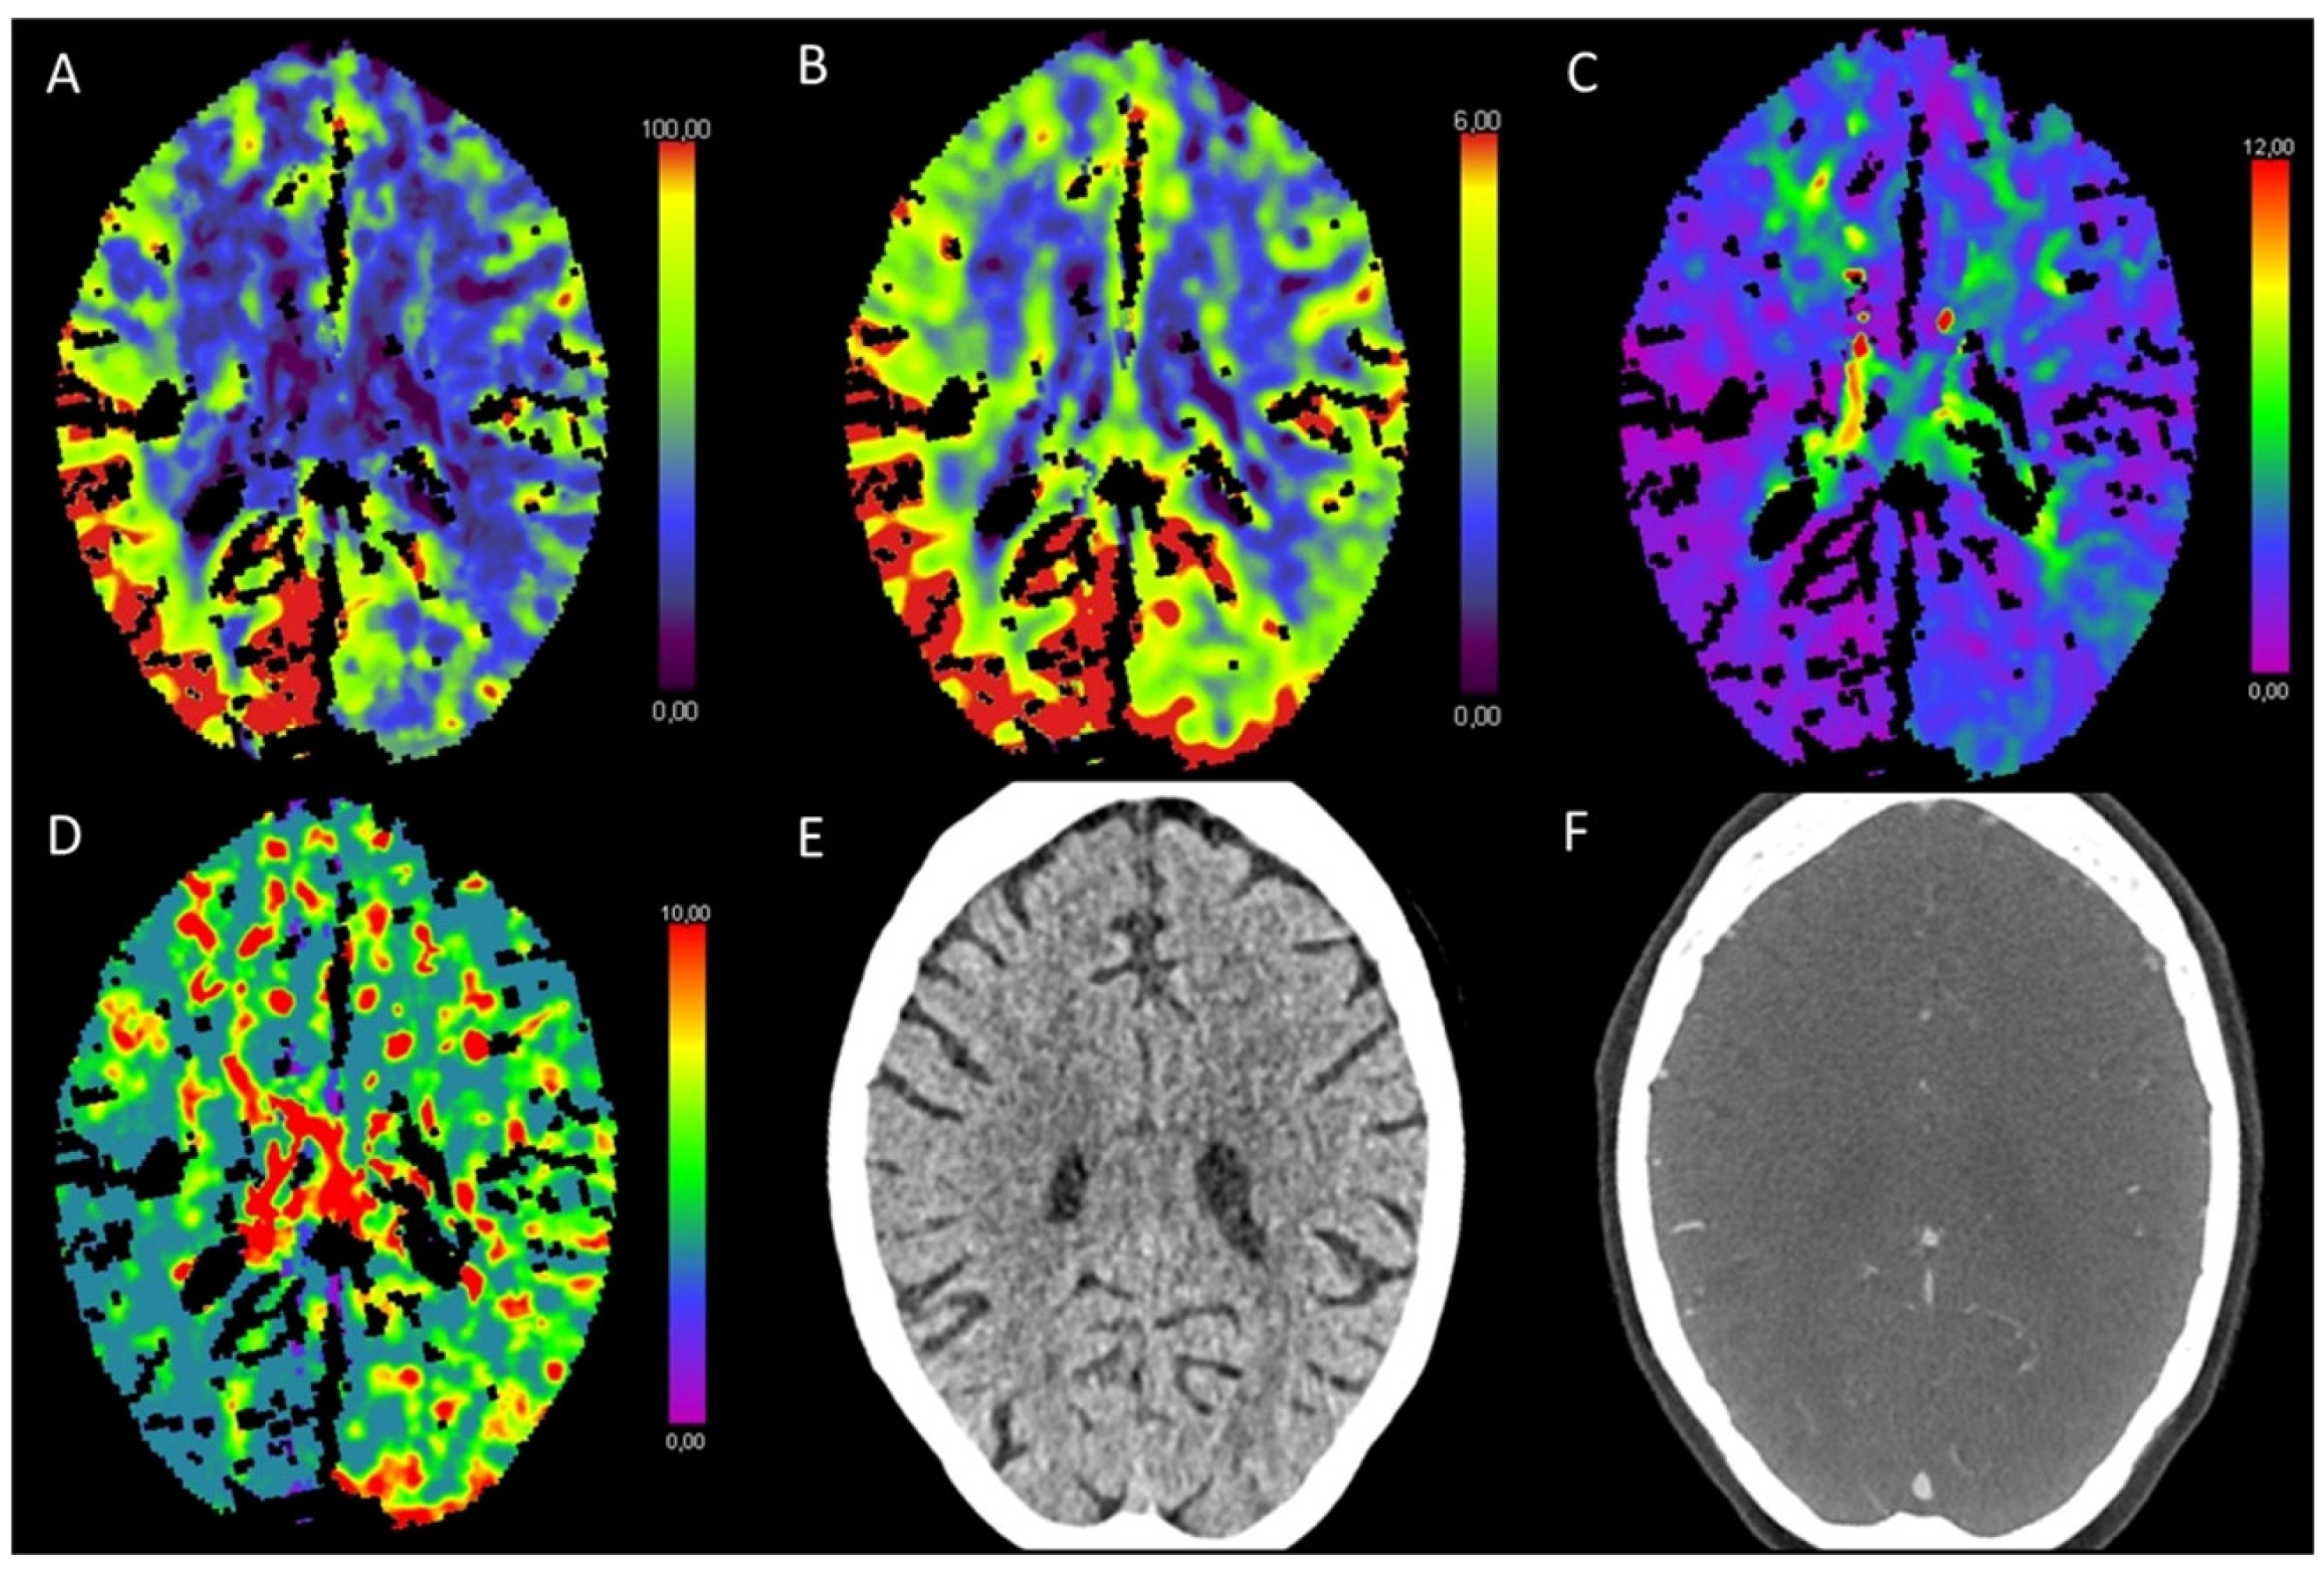

3.5. Hypotensive Cerebral Infarction (HCI) with Watershed Infarcts/Border Zones

| Hypotensive cerebral infarction (HCI) with watershed infarcts/border zones | ↑ | ↓/- | ↑ | ↑ |